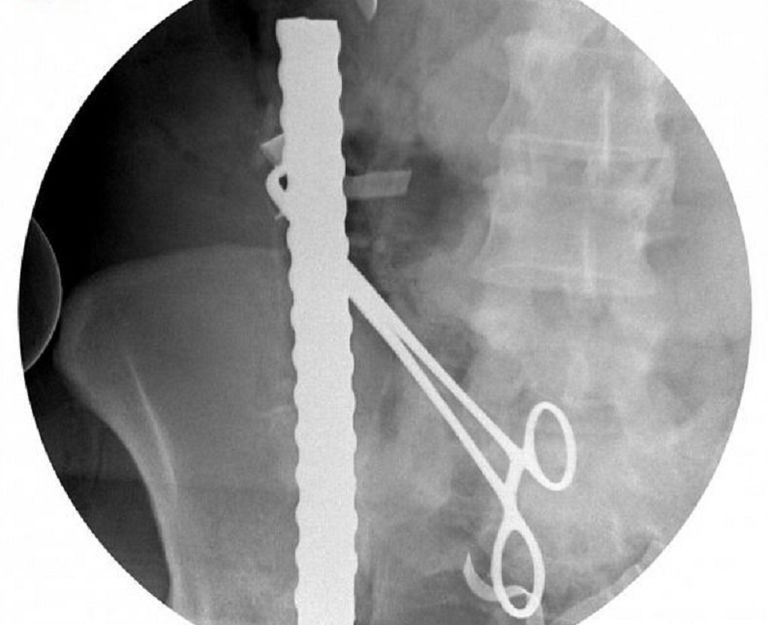

وأوضحت الدكتورة نورة السبيعي أن السيخ الأول اخترق الجزء الأيمن من منطقة الفخذ وصولا إلى شرايين الكلية اليمنى وتسبب في إصابة طفيفة في الاثني عشر، بينما اخترق السيخ الثاني منطقة البطن السفلى، ما أدى إلى إصابة الأمعاء الدقيقة في 4 مناطق واستقر في الجزء العلوي من المعدة.

وأشارت إلى أن السيخ الثالث اخترق الحوض من الجهة اليسرى، ما أدى إلى كسر مضاعف في الحوض، واستقر بمحاذاة العمود الفقري دون اختراقه، وفقا لوكالة الأنباء السعودية.

ولفتت السبيعي إلى أنه تم استخراج السيخ الأول بعد السيطرة على الشرايين الكبرى، بينما تمت إزالة السيخين الآخرين بعناية شديدة كي لا تؤثر على الأعضاء المحيطة بالمنطقة المصابة.